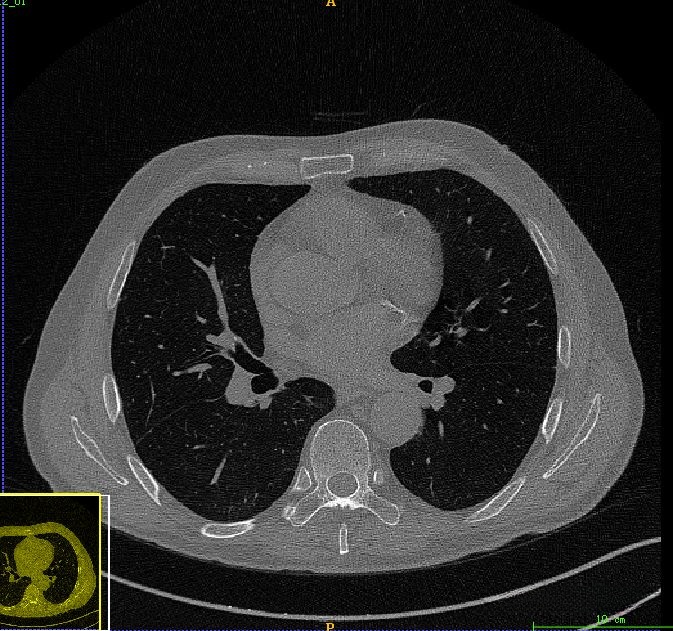

在原始CT图像中可见的是较大的噪声水平,在这种情况下会影响到后续的肺部分割过程。为此,在此阶段我们采用了中值滤波作为预处理手段以减少这一问题的影响。经过中值滤波处理后可以看出大部分噪声已被有效抑制然而这种现象并不会对我们后续的目标造成困扰因为我们的主要目标是提取出完整的肺部区域范围因此在这一操作完成后我们可以合理地忽略掉其中可能存在的残留干扰信息

最后得到肺部区域图像如下所示。